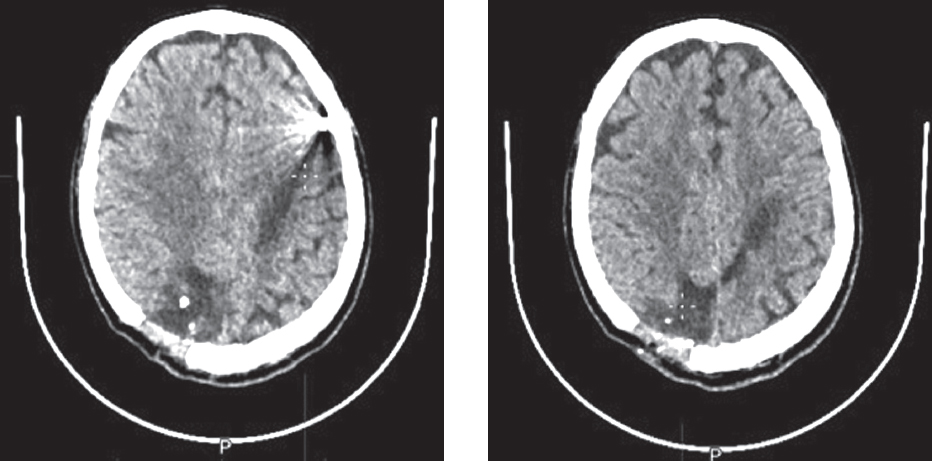

Notably, 24 patients with non-removable metal fragments and 16 patients with bone fragments in the brain had no seizures. Moreover, these patients had no epileptiform activity on EEG and did not receive AEDs (Figures 7–10). This emphasizes that a genetic predisposition to epileptic system formation following an injury, with seizures caused by insufficiency of the innate antiepileptic system, plays a significant role in the development of PTE.

Fig. 7. Patient D. Head CT — condition after resection-decompression trepanation of the parietal bone on the right; a massive area of cystic-atrophic changes is noted in the right occipital, both parietal lobes and the frontal lobe on the left with approximate dimensions of 105 × 20 mm; in the cortical sections of the left frontal lobe, a foreign body of metallic density with dimensions of 9 × 8 mm is noted

Рис. 7. Пациент Д. КТ головы — состояние после резекционно-декомпрессионной трепанации теменной кости справа; отмечается массивный участок кистозно-атрофических изменений в правой затылочной, в обеих теменных долях и лобной доли слева приблизительными размерами 105 × 20 мм; в кортикальных отделах левой лобной доли отмечается инородное тело металлической плотности размерами 9 × 8 мм

Fig. 9. Patient F. Head CT — in the right hemisphere of the cerebellum, a hypodense wound channel was revealed with the presence of foreign bodies of bone density, single and grouped, with a total size of up to 4 × 6 mm; taking into account the ricochet wound, the wound channel goes upward through the cerebellum and the right cerebral peduncle with the presence of a foreign body of metallic density measuring 8 × 9 mm, located cranial to the enveloping cistern, to the right of the pineal gland

Рис. 9. Пациент Ф. КТ головы — в правом полушарии мозжечка выявлен гиподенсный раневой канал с наличием инородных тел костной плотности, единичных и группированных, общими размерами до 4 × 6 мм; с учетом рикошетирующего ранения, раневой канал идет вверх через мозжечок и правую ножку мозга с наличием инородного тела металлической плотности размерами 8 × 9 мм, расположенного краниальнее охватывающей цистерны, справа от шишковидной железы